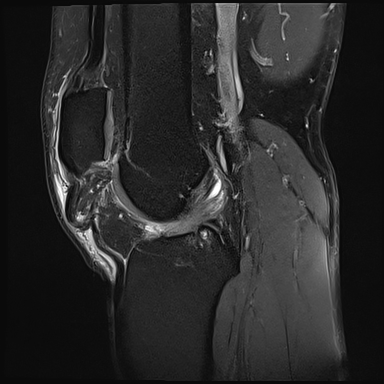

L’ultrason ou l’IRM peut confirmer le diagnostic de lésion du tendon rotulien et de différencier une rupture partielle d’une rupture complète. Le traitement est chirurgical.